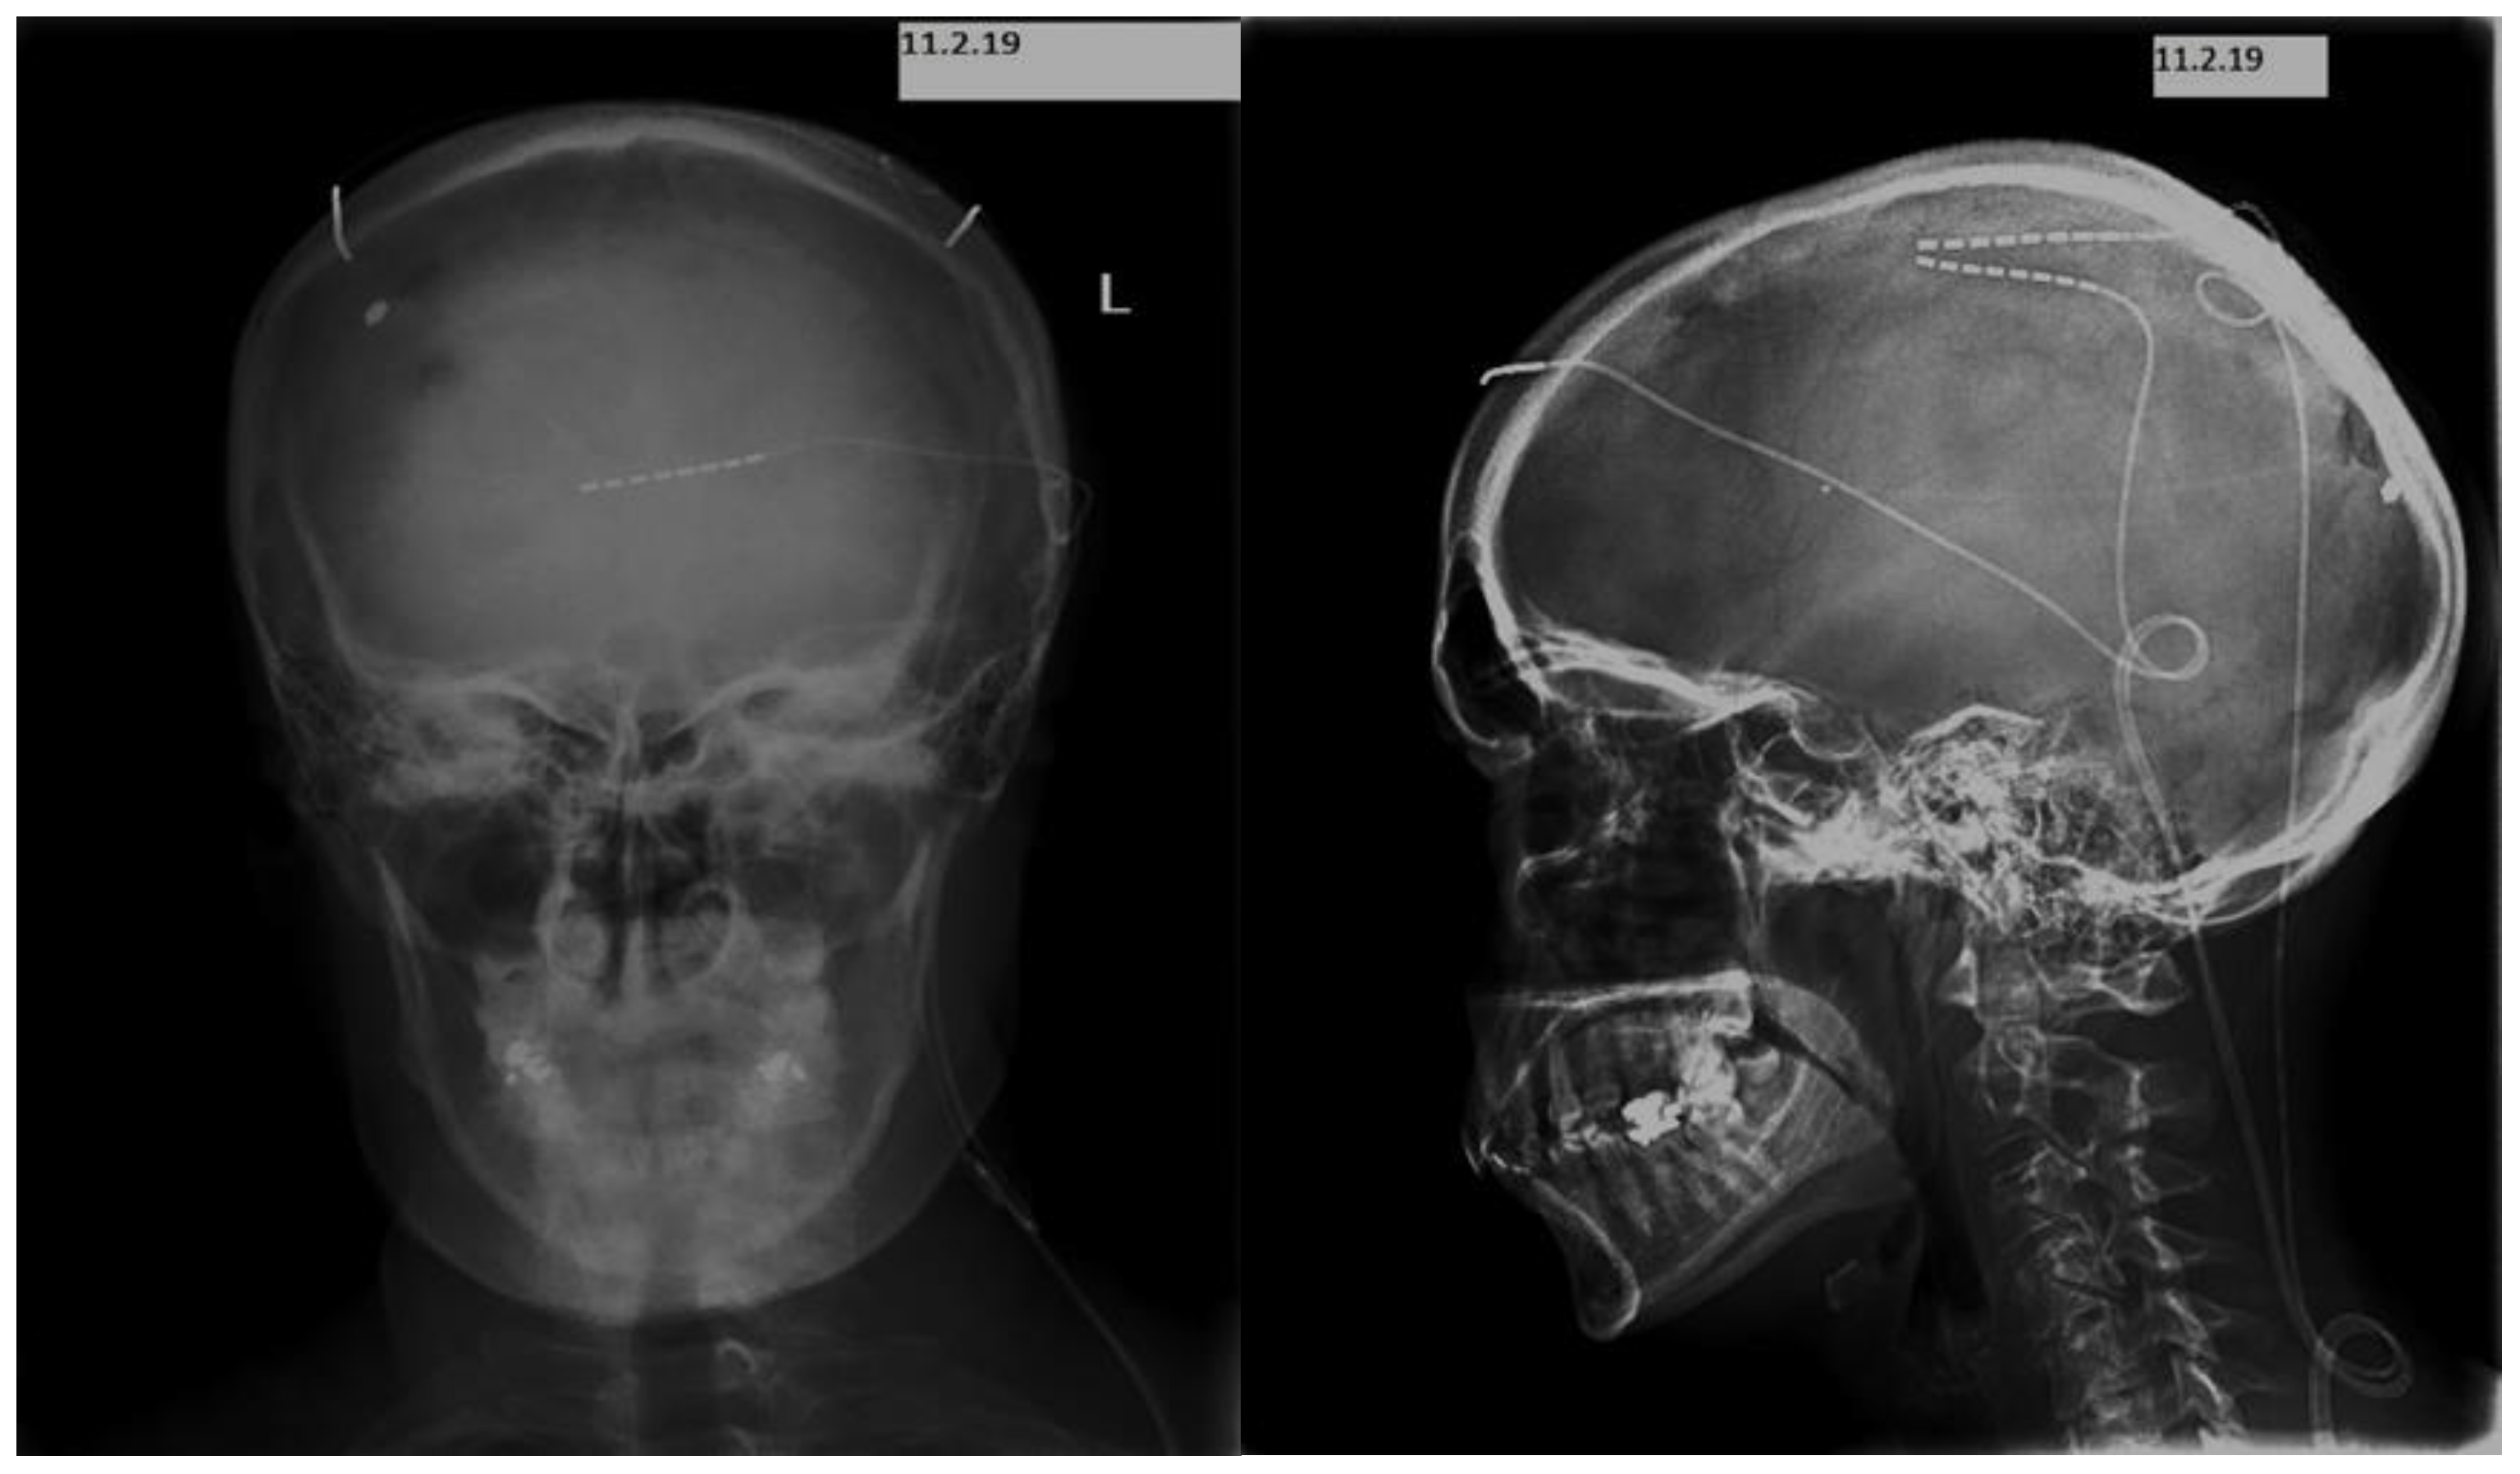

2. Case Presentation

Implantation Techniques and Devices